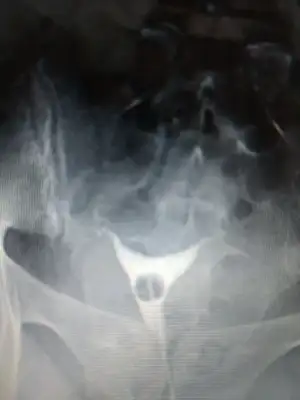

Onun hatlar karışık biraz. Çekim sonrası radyologun mesai saati bittiği için rapor yetişmemiş. Pazartesi alacak sonucunu. Kendi doktoru tüplerden birinde tıkanıklık var gibi konuşmuş ama başka doktorlara da göstermiş, basınçla açılmış demişler

pazartesi herşey sonuçlancak demek. Açılmıştır kuzum bak sorunun nerde olduğu anlaşıldı en azından en kısa zamanda gelecek beben